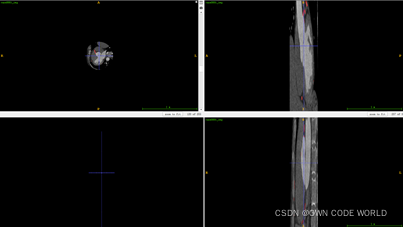

17.在这个模型中,测试出来的结果为下图.nii.gz格式的,因此我们可以使用ITK-SNAP软件来查看。

下面时使用ITK-SNAP软件来查看的结果图:

Img.nii.gz

pre.nii.gz

Img.nii.gz+ pre.nii.gz

Img.nii.gz+ gt.nii.gz

因为这组数据的dice有86%,所以效果还不错。